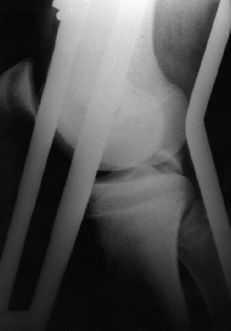

Figura 2. Niño de 15 años de edad con fractura avulsión del LCP y fractura asociada de la diáfisis del fémur. A: Radiografía preoperatoria. B: Radiografía a los 6 meses de evolución.